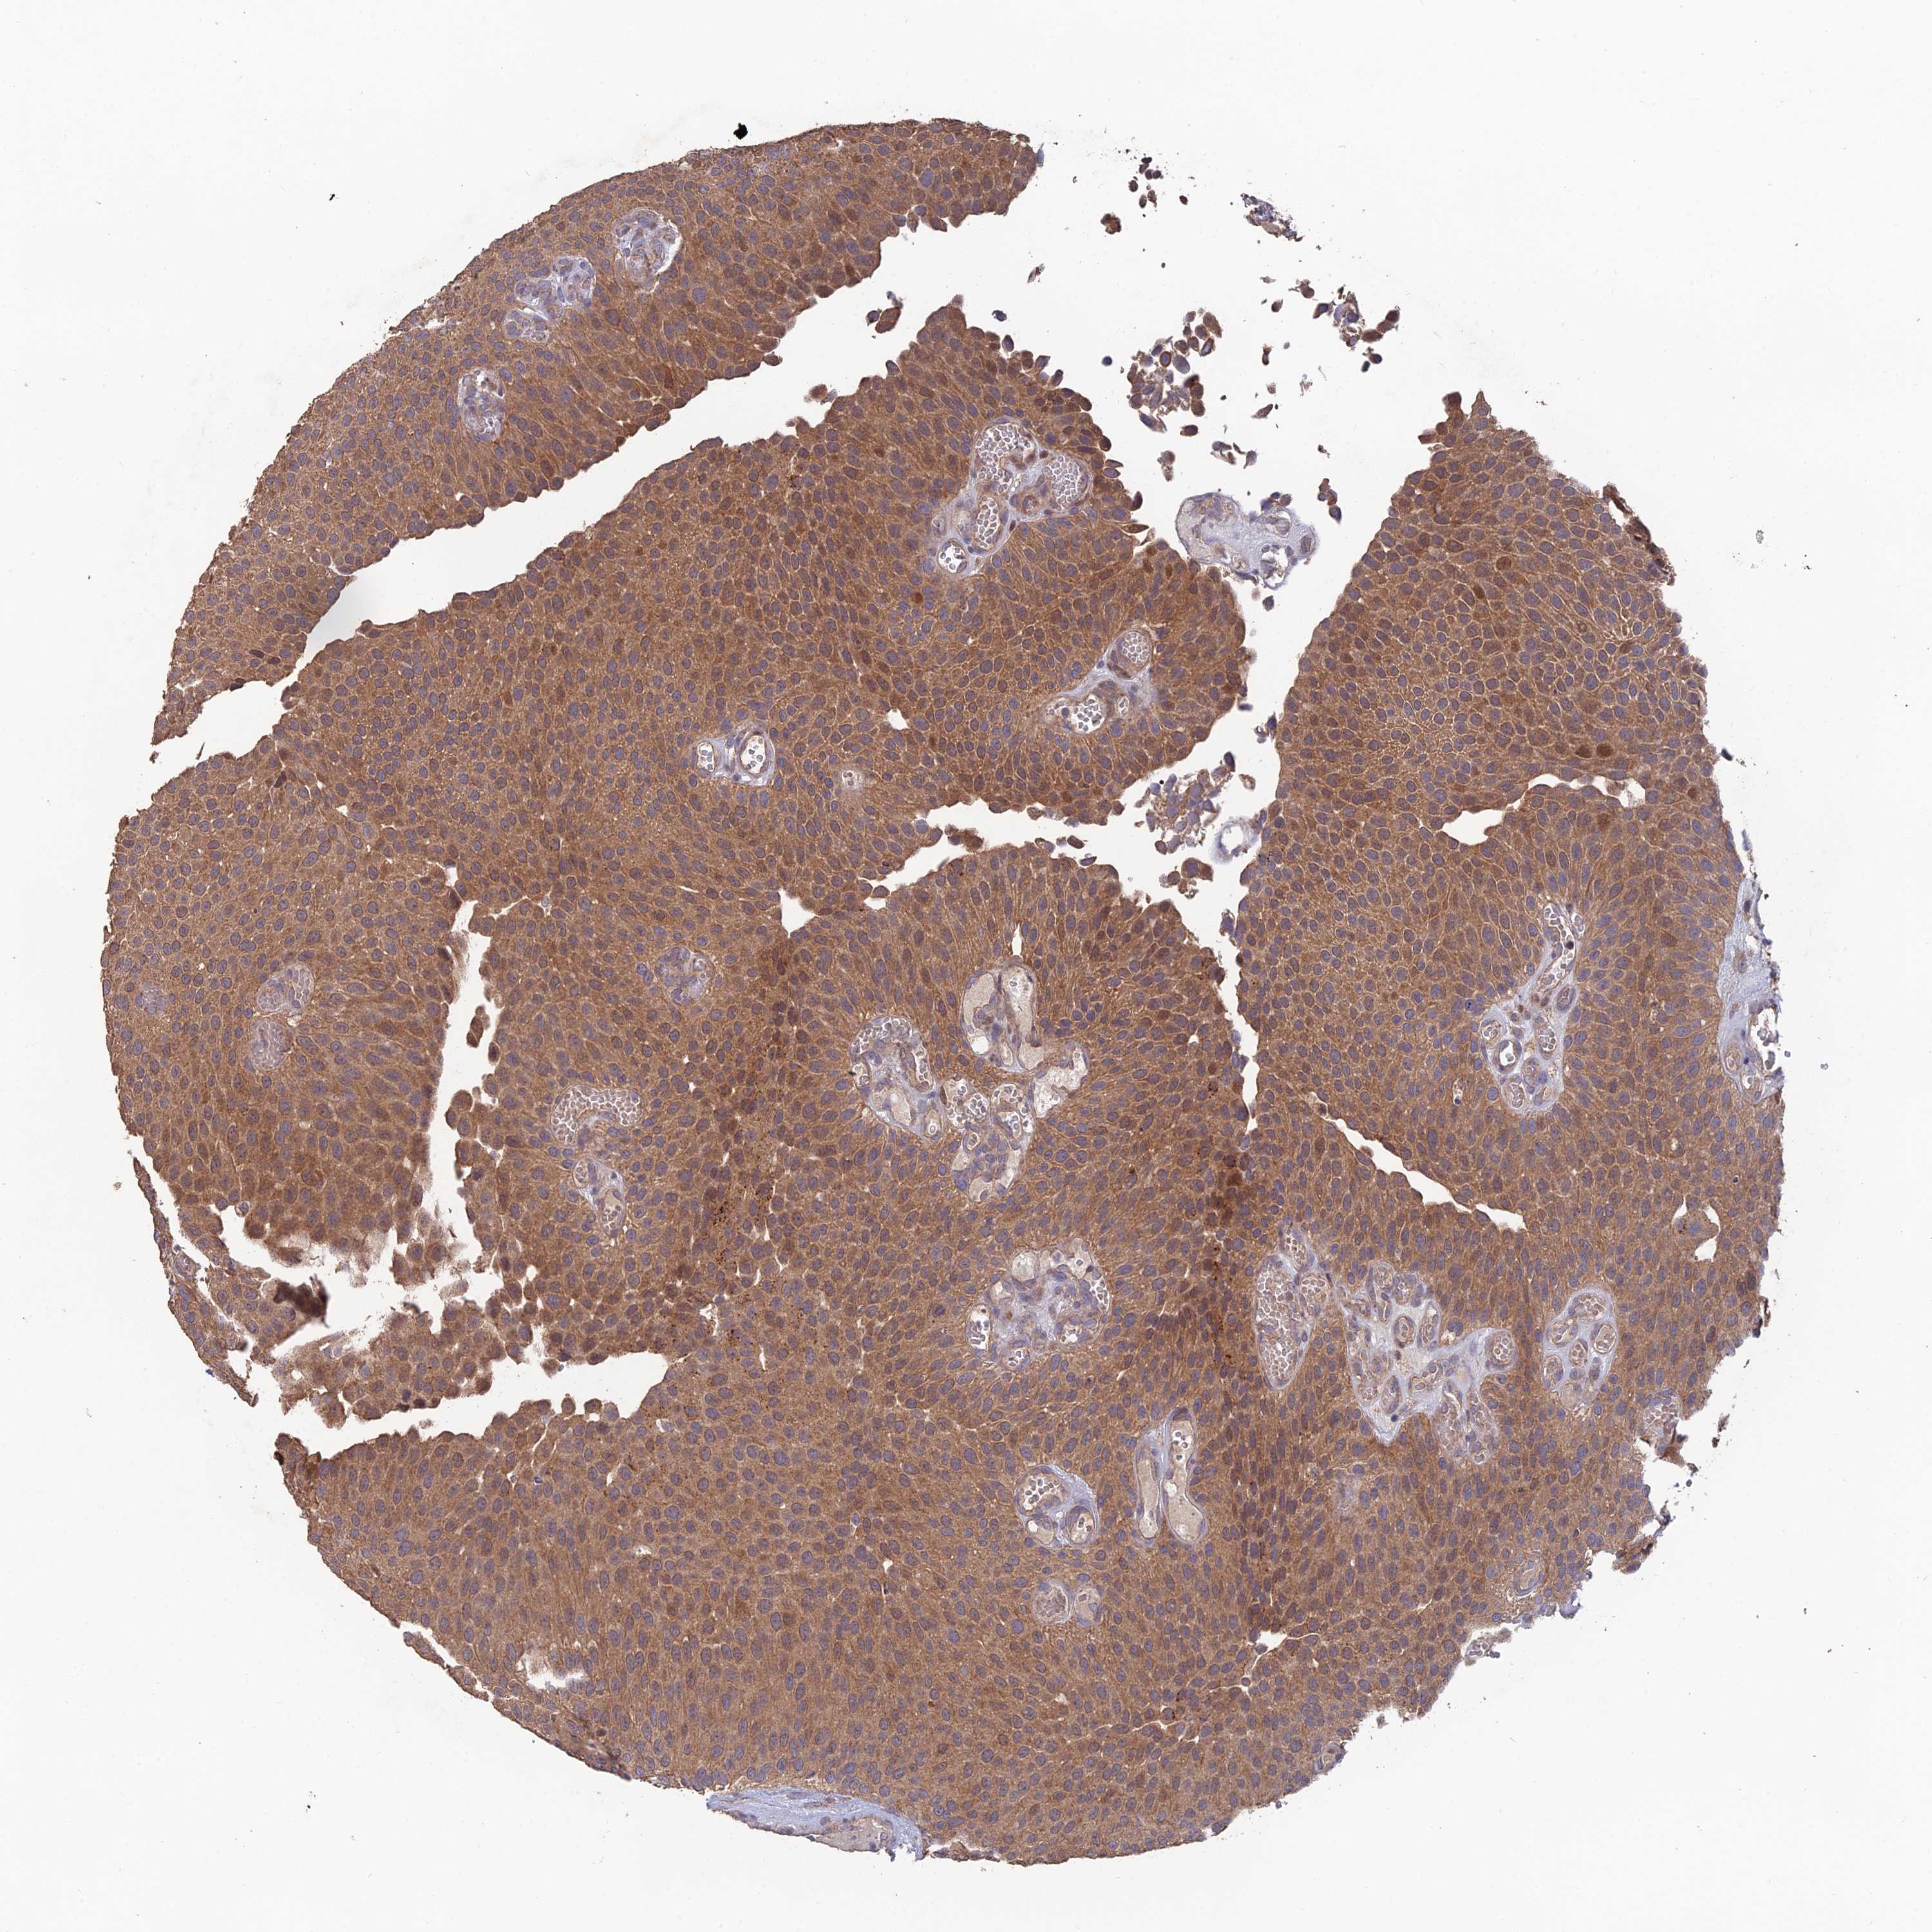

UROTHELIAL CANCER - Protein expressioni

A mouse-over function shows sample information and annotation data. Click on an image to view it in a full screen mode. Samples can be filtered based on level of antibody staining by selecting one or several of the following categories: high, medium, low and not detected. The assay and annotation is described here.

Note that samples used for immunohistochemistry by the Human Protein Atlas do not correspond to samples in the TCGA dataset.

Antibody stainingi

Antibody staining in the annotated cell types in the current human tissue is reported as not detected, low, medium, or high, based on conventional immunohistochemistry profiling in selected tissues. This score is based on the combination of the staining intensity and fraction of stained cells.

Each image is clickable and will lead to virtual microscopy that enables deeper exploration of all samples and also displays staining intensity scores, fraction scores and subcellular localization as well as patient and tissue information for each sample.

Antibody HPA042295

Staining

High

Medium

Low

Not detected

Intensity

Strong

Moderate

Weak

Negative

Quantity

>75%

75%-25%

<25%

None

Location

Nuclear

Cytoplasmic/membranous

Cytoplasmic/membranous,nuclear

Urothelial carcinoma, High grade

Urothelial carcinoma, Low grade